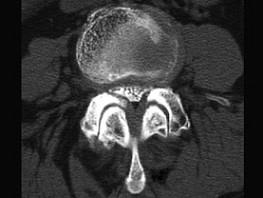

问题 腰椎间盘突出症(如图1)与腰椎管狭窄症(如图2)临床症状的主要不同点为 ( )

选项 A、双下肢无力情况 B、二便是否障碍 C、鞍区感觉改变情况 D、腰痛及下肢放射痛的程度 E、有否间歇性跛行

答案 E